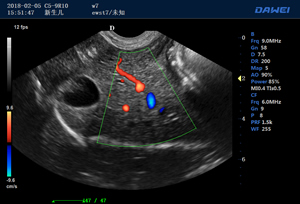

·支持B、C、PW、CW、寬景成像